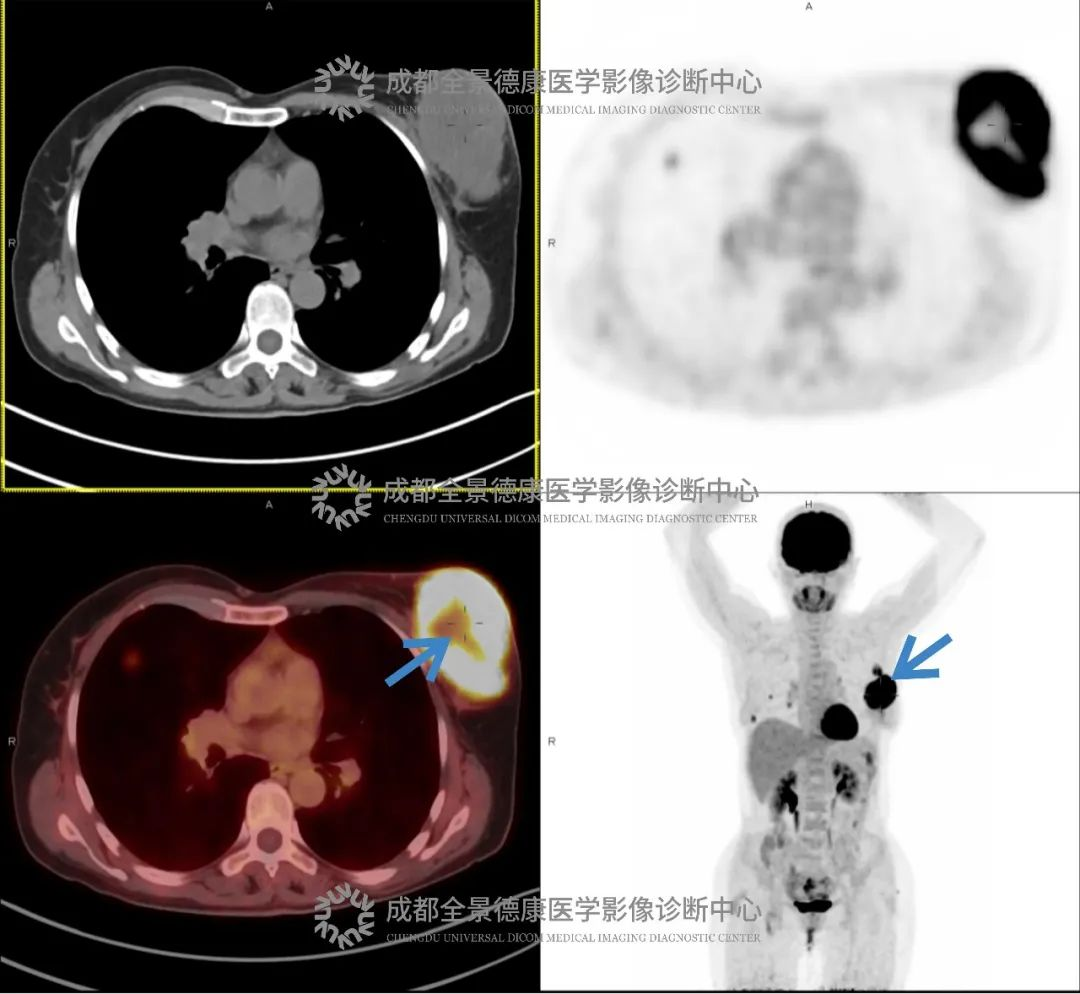

乳腺癌转移案例

夏女士(化名),4 个月前偶然发现左侧乳腺有包块,无疼痛、发热等症状。没太在意,但随着时间推移,包块越长越大,夏女士这才去医院,结果被诊断为「左侧乳腺癌」。为进一步评估全身转移情况,我们为夏女士进行了 PET/CT 检查。

影像:

左乳软组织肿块伴坏死,FDG 代谢活跃

诊断:

考虑乳腺癌,伴左乳头侵犯,左侧胸大肌受累可能;并伴:(1)左侧腋窝淋巴结转移;(2)双肺转移瘤。

夏女士平素未定期进行乳腺癌筛查,在乳腺发出「长出包块」的信号后也未引起重视,更遑论及时诊治,导致确诊时已出现淋巴结转移和肺转移,延误了治疗时机。